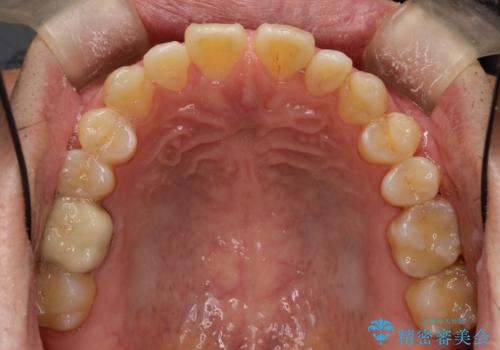

前歯の隙間 インビザラインにて整った歯並びへ

- 前歯の隙間が気になるとのことで来院されました。

インビザラインにて矯正治療を行うこととしました。

下の歯と歯の間にわずかに隙間をつくり、上の前歯の隙間を閉じました。